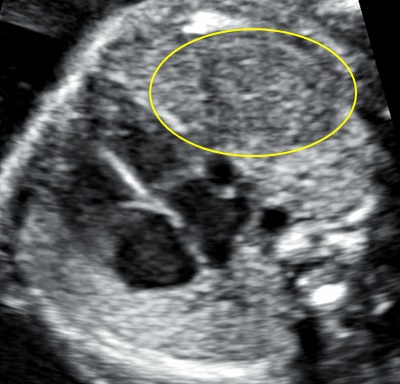

Проанализируйте изображения сердца и установите диагноз

32 недели

Ответ на вопрос 1

- У плода множественная рабдомиома.

- Комментарий: мы видим нормальное соотношение камер сердца, магистральные сосуды выходят правильно, гемодинамика не изменена.

- Яркая округлая структура в полости левого желудочка может быть ошибочно расценена как гиперэхогенный фокус. Однако, при сроке 32 недели такие крупные гиперэхогенные фокусы не встречаются.

- В полости правого желудочка рядом с модераторным пучком определяется еще одна рабдомиома

- Прогноз при данном пороке благоприятный, т.к. расположение рабдомиом не нарушает нормальную гемодинамику, однако требуется консультация генетика, тщательное ультразвуковое исследование мозга, МРТ мозга для исключения туберозного склероза.